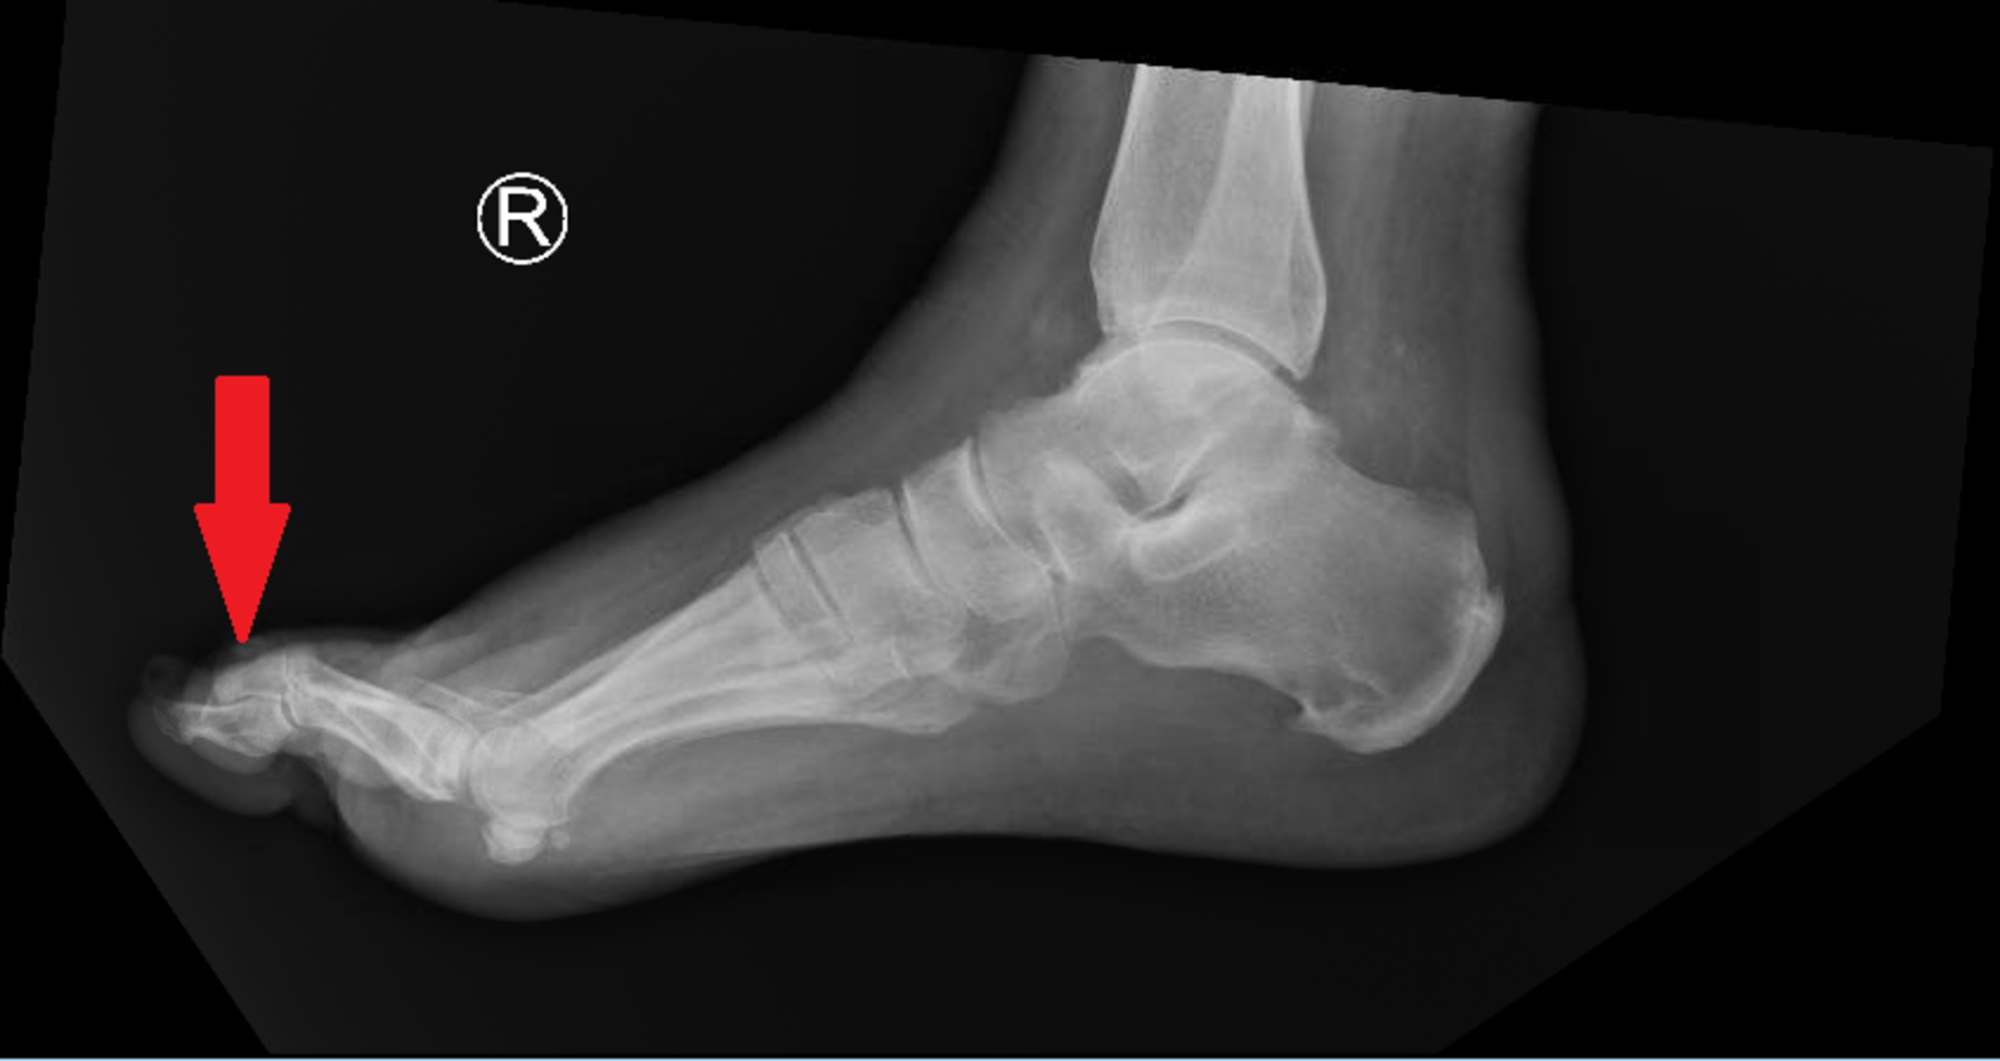

Various features of NC coalition on radiograph. Irregular articular Foot Nc Joint The main goals of the surgery are to: nc joint arthrodesis, as described by hoke (1) in 1931, is a utility procedure used for the correction of medial column insufficiency or realignment of forefoot. The joint is located in the mid part of. There is little in the. the nc fusion is the most powerful and effective fusion. Foot Nc Joint.